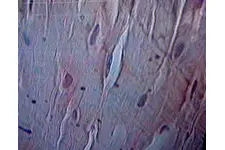

Kıkırdak Doku Çeşitleri Kıkırdak doku, bağ dokuları arasında yer alan, esnek ve dayanıklı bir yapıya sahip olan dokulardır. Farklı türleri ve işlevleri, vücudun çeşitli bölgelerinde önemli roller üstlenmektedir. Bu makalede, kıkırdak dokunun çeşitleri ve özellikleri detaylı bir şekilde ele alınacaktır. Kıkırdak Doku Türleri Kıkırdak doku üç ana türde sınıflandırılmaktadır: hyalin kıkırdak, elastik kıkırdak ve fibröz kıkırdak. Her bir tür, farklı yapısal özelliklere ve işlevsel amaçlara sahiptir.

Kıkırdak Dokunun Özellikleri Kıkırdak dokunun bazı ayırt edici özellikleri şunlardır: